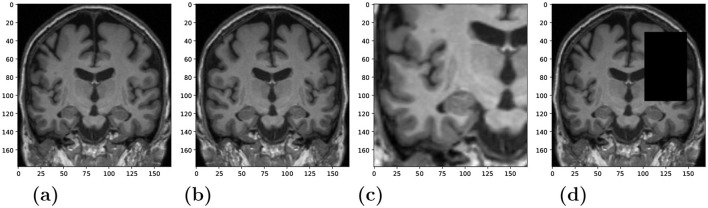

Methods: We investigated if the SSL models can be applied to distinguish between different neurodegenerative disorders in an interpretable manner. Our method comprises a feature extractor and a downstream classification head. A deep convolutional neural network, trained with a contrastive loss, serves as the feature extractor that learns latent representations. The classification head is a single-layer perceptron that is trained to perform diagnostic group separation. We used N = 2,694 T1-weighted MRI scans from four data cohorts: two ADNI datasets, AIBL and FTLDNI, including cognitively normal controls (CN), cases with prodromal and clinical AD, as well as FTLD cases differentiated into its phenotypes.

Results: Our results showed that the feature extractor trained in a self-supervised way provides generalizable and robust representations for the downstream classification. For AD vs. CN, our model achieves 82% balanced accuracy on the test subset and 80% on an independent holdout dataset. Similarly, the Behavioral variant of frontotemporal dementia (BV) vs. CN model attains an 88% balanced accuracy on the test subset. The average feature attribution heatmaps obtained by the Integrated Gradient method highlighted hallmark regions, i.e., temporal gray matter atrophy for AD, and insular atrophy for BV.